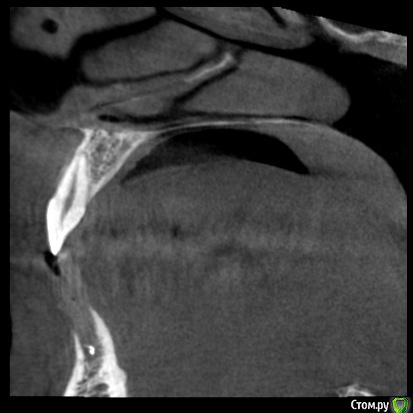

nemorr Опубликовано 14 сентября, 2020 Поделиться Опубликовано 14 сентября, 2020 Кт зубовhttps://yadi.sk/d/6aZXi03bqS5B5Q Здравствуйте.Хотел обратиться по поводу проблем с зубами. Пред история.Началась проблема с 31 зуба в марте этого месяца.Был пульпит, пролечили. Но спустя 2 недели он заболел вновь. На снимках выглядел хорошо, я долго терпел он не прошел, приняли решение очистить, канал был один. Заложили уже йодекс на подольше. Зуб в итоге прошел через 1.5 месяца должен был его долечить, но ковид испротил все планы. Провалялся в больнице, месяц потом ещё месяц болел дома. В августе зуб опять заныл, поменял лекарство на кальсепт стало ещё больнее, на 3d виден выход кальсепта за верхушку корня, не большое потемнение под корнем, возможно гранулёма (в марте не было) Тактик лечения было несколько. 1)Так как есть проблемы с прикусом и суставом. 2) После каждого лечения 31 зуб сдвигался немного и мешал жевать (его потом чуть чуть подпиливали)Было предположение что я настукиваю прикусом зуб и он из-за этого не проходит. В очередной раз почти вывели его из прикуса, нажимать я на него перестал, но боль не прошла. В итоге его открыли так как при попытки сменить лекарство ещё раз при чистом канале эскудат выступил видимо из под корня зуба. Решили оставить открытым полоскать. Боль после этого реально прошла! Неделю я радовался как ребенок и собирался уже идти закрывать зуб обратно. Но уехал за город там видимо подмерз зуб разболелся с новой силой, я плюнул на всё и его удалил. Под зубом была не большая гранулёма. Через 3-5 дней боль снизу ушла.Это всё была пред история. Через неделю у меня заболел 21 зуб. Он у меня живой не депульпированный кариеса на нем нет!. Единственное что связывает его с 31 зубом это прикус.Боль потихоньку начала нарастать. Характер боли: Сам зуб при надавливании ощущается дискомфорт, как будто что мешает. Но после того как его по шевелишь боль усиливается и сильно воспаляется боль распространяется на соседние зубы. Боль не стреляющая но может быть не только вопалительной но и жгучей. Голова конечно от этого болит. Если зуб не тревожить то боль уменьшается.Делали ЭОД 2 раза 8 и 6 мкА показало. Ссылка на комментарий

nemorr Опубликовано 17 сентября, 2020 Автор Поделиться Опубликовано 17 сентября, 2020 А что нибудь пояснить?Лекарство в лунке 31 у меня какое-то временное. Или каласепт или йодекс. Врачи говорят что само в растворится.По поводу кисты/полипа в правой пазухе. У меня хронический насморк давно. Чуть меньше года назад была в левой большая, а в правой минимум. ЛОР хирург сказал что если нормально дышишь лучше не удалять, а применять терапевтическое лечение. Что я и делал, тафен назаль. Сейчас вот картина обратная выросла справа, а слева уменьшилась. Но болит именно 21 зуб который сверху слева. Боли уже напоминают невралгию. Невролог прописал фенлипсин пью. Но невролог сказал зуб всё равно депульпировать. Понажимал на лицо сказал на истинную невралгию не похоже, пишет невралгия из-за зуба.Но стоматологи не видят проблемы в 21 зубе не какой. Ссылка на комментарий